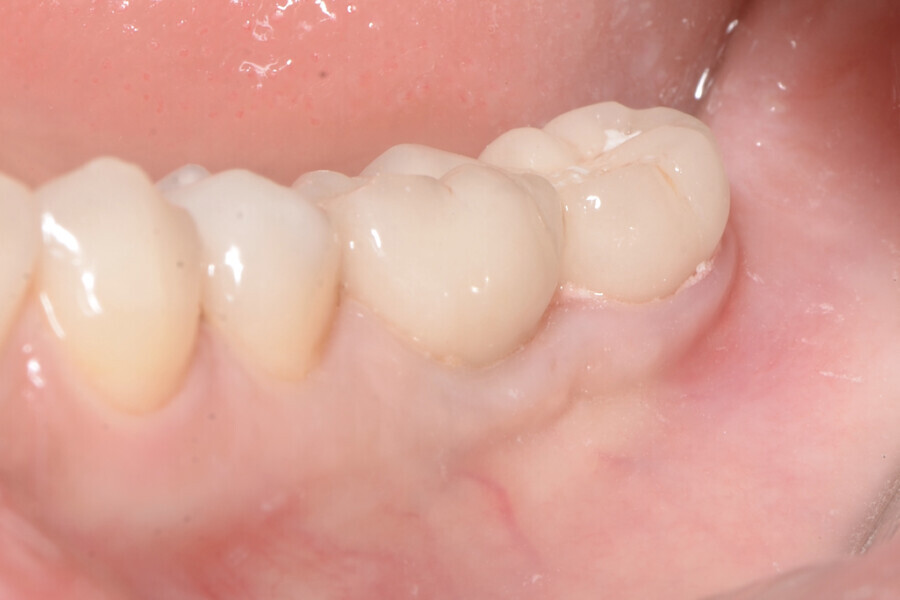

Aspect clinique de la zone des tissus mous péri-implantaires lors du suivi à cinq ans. (Photo : Dr Cosimir Dima)

Dix jours après l’intervention, les sites donneur et receveur étaient parfaitement cicatrisés (Figs. 15 et 16). Des visites de contrôle ont été prévues deux et quatre semaines plus tard, suivies de visites à trois, six et douze mois, puis tous les six mois pendant cinq ans (Figs. 17 à 20).

La profondeur de sondage du site péri-implantaire a été mesurée au niveau du point médian inter-proximal, et la valeur la plus élevée entre le bord des tissus mous et le fond du sulcus péri-implantaire a été retenue. Une lime endodontique ISO n° 15 a été utilisée pour évaluer l’épaisseur de la muqueuse péri-implantaire vestibulaire à 2 mm des bords des tissus mous en mésial, distal et médial de la plate-forme de l’implant (point de référence). La muqueuse kératinisée a été évaluée au début du traitement, puis lors des suivis au moyen d’une sonde parodontale. Les mesures ont été prises verticalement au niveau du point médio-vestibulaire, depuis la plate-forme de l’implant jusqu’au bord libre de la gencive. Elles ont été effectuées en préopératoire, immédiatement après l’intervention, puis à quatre semaines, un an et deux ans par la suite. Les paramètres cliniques (largeur de la muqueuse kératinisée, volume de la muqueuse, et recouvrement de la récession gingivale) ont été enregistrés au début du traitement, et lors de chaque visite de suivi. La largeur initiale de la muqueuse kératinisée était minimale (1 mm). À quatre semaines, le gain de largeur de la muqueuse kératinisée était de 2 mm, puis de 3 mm après un an, et de 4 mm après cinq ans.

À quatre semaines, le gain de volume de la muqueuse était de 3 mm, puis de 4 mm après un an, et de 5 mm après cinq ans. Le recouvrement de la récession était déjà complet après quatre semaines, et l’était toujours après un an et après cinq ans.